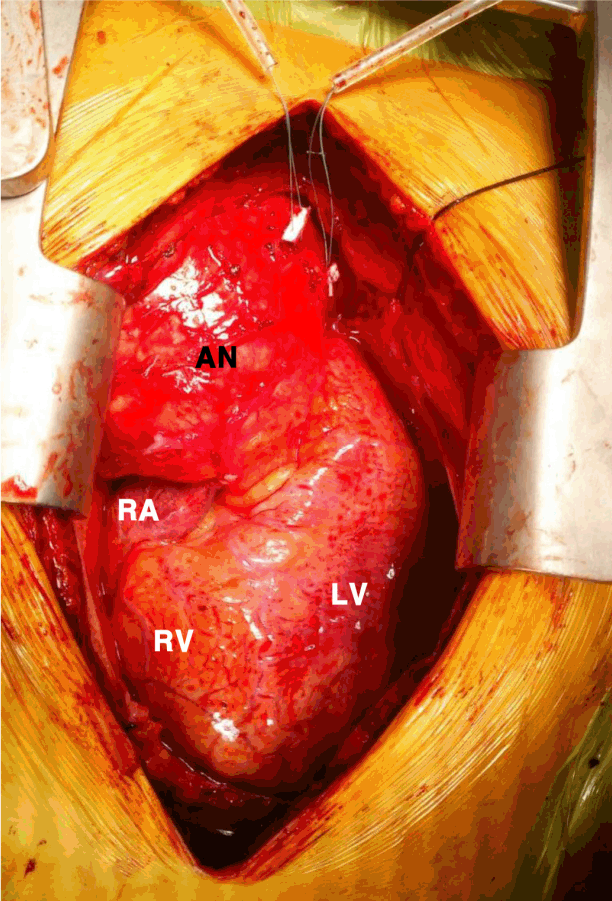

Emergent surgical repair was performed. Surgically, the aneurysm wall was adhered to the pericardium, which was filled with a bloody effusion. The wall of the aneurysm was extremely thin and easily torn, even with gentle manipulation. Vascular wall thickening was noted on the PET-positive aortic segments (Fig. 2).

Figure 2.

Intraoperative image of the ascending aortic aneurysm. AN, aneurysm; RA, right atrium; RV, right ventricle; LV, left ventricle.